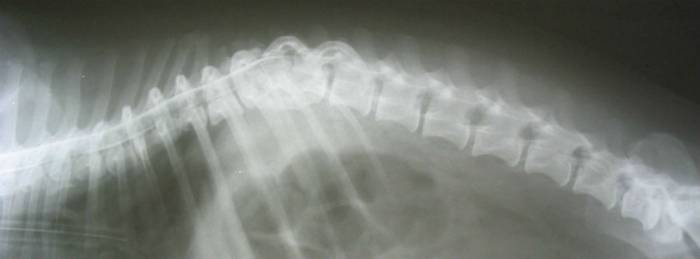

Дисторсия на снимке рентгенографии

- Рентгенография. Выполняется для проверки наличия повреждения или выпадения отдельных позвонков, так же с ее помощью фиксируют точное положение травмы.

- Магнитно-резонансная или компьютерная томография. Делает то же самое, что и рентгенография, но также способна показать состояние связочного аппарата и узнать, не имеется ли его повреждений.

- Рентгенография позвоночного столба. Простой, дешевый и высокоточный способ диагностики. Выполняется рентгенография травмированного отдела позвоночника. При дисторсии рентгенография фиксирует целостность позвонков, их нормальное расположение.

- Магнитно-резонансная томография. Сравнительно дорогой способ исследования. В отличие от рентгенографии не оказывает негативного воздействия на организм, так как в процессе не используются рентгеновские лучи. Используемое при диагностике магнитное поле не имеет отрицательных последствий для пациентов. При МРТ видны все отделы позвоночника, а также спинной мозг, связки, мышцы, окружающие позвоночный столб. Это позволяет определить наличие патологических процессов и последствий травм.